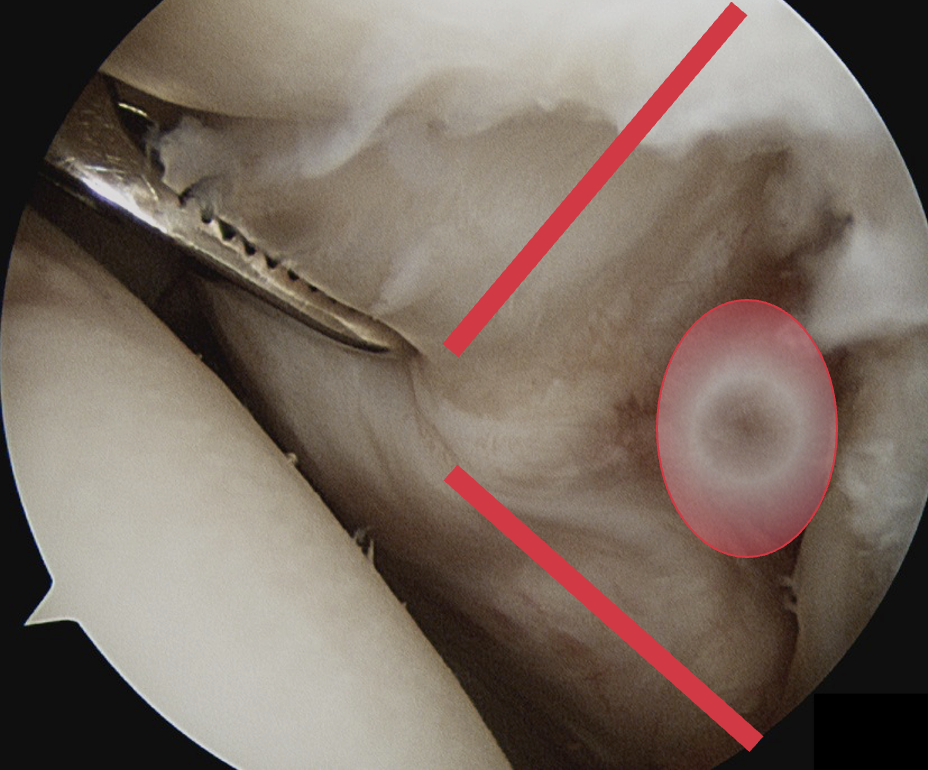

1. Minimally retracted subscapularis tear

- anterior rotator cuff portal for footprint debridement and anchor insertion

- anterolateral portal / portal of Wilmington for biceps / suture passage

- tag biceps for later tenodesis

- debride footprint on lesser tuberosity

- insert anchor through anterior portal

- pass sutures from anterolateral portal with birdsbeak or from lateral portal with suture passer

- tie from anterior portal

- +/- lateral row / double row repair

Anterolateral portal of Wilminton at anterolateral border of the acromion used to tag and release biceps

Insert anchor through anterior portal into subscapularis footprint

Suture passage through anterior portal or anterolateral portal and tie sutures through anterior portal